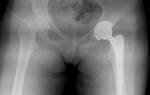

Особенности клинико-рентгенологической картины лежат в основе классификации артроза кистей. Всего выделяют 3 стадии патологии, для каждой из которых характерны определенные симптомы и рентгенологические признаки. Также общепринята классификация артроза Kellgren и Lawrence. Эти авторы выделяют 0 стадию заболевания, при которой рентгенологические признаки поражения костей и хрящей отсутствуют, а клинические проявления выражены слабо.

При артрозе кистей на первой стадии изменяется состав синовиальной жидкости. В ней содержится недостаточное для нормального функционирования хрящей количество питательных веществ. На полученных рентгенографических изображениях отмечается нечеткое сужение суставной щели, формирование начальных остеофитов на краях костных структур.

2 стадия

В местах локализации отеков формируются костные образования (узелки Гебердена), которые обычно расположены симметрично на левой и правой кисти. Мелкие суставы пальцев заметно деформируются, что становится причиной ограничения подвижности. Артроз проявляется нарушением функций околосуставных мышц, их умеренной атрофией.

На рентгенографических снимках отчетливо визуализируются множественные остеофиты, субхондральный остеосклероз в костных тканях, заметное сужение суставной щели.

3 стадия

При проведении рентгенологического исследования выявляются обширные остеофиты, полное или частичное сращение суставной щели, субхондральные кисты, «суставные мыши» (свободно перемещающиеся твердые частицы). Суставная площадка сильно деформирована, что приводит к нарушению соотношения между анатомическими структурами. В дегенеративный процесс оказываются вовлечены связки и сухожилия — они укорачиваются, становятся менее прочными.

Артроз кисти 3 степени.